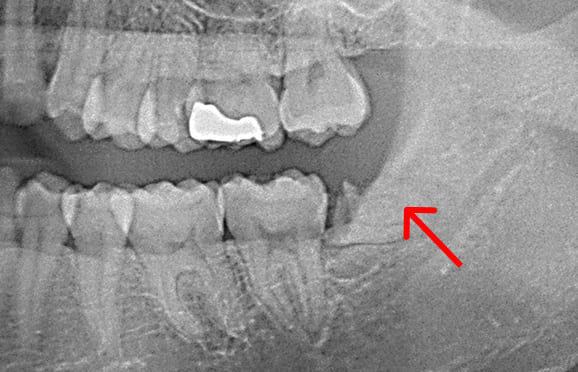

01 左下7の近心根にエンジンファイルの破折

02 ファイル除去時

※根尖周囲の透過像はまだ残存

03 最終の根充剤を充填

※根尖透過像が小さく治癒方向へ向かっている